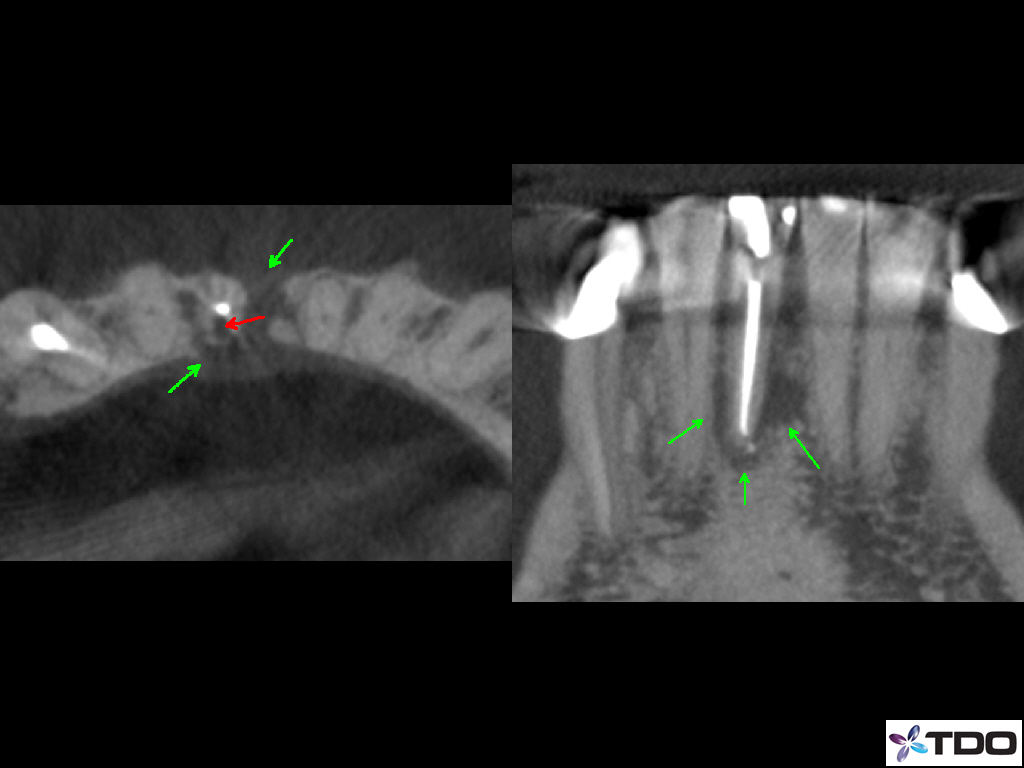

A root canal infection can cause tooth discoloration and a tremendous amount of bone loss.  The tooth can be effectively bleached.  With careful treatment, we can predictably get the bone to heal.